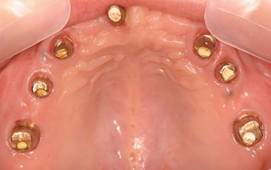

白金加金のアバットメント(土台)

上顎